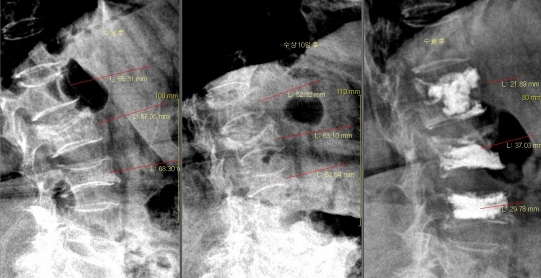

본원에서는 병적 골절 예방읠 위하여 X-선 흡수계측법(DEXA)에 의한 전신골밀도 측정기를 도입 운영중에 있으며 경미한 외상에도 골절 되기 쉬운

요추부 및 고관절등의 7부위를 측정할 수 있는 최신 시스템을 갖추고 있습니다.

-치료효과 판정을 위한 추적검사(Follow-up)는 central bone(spine, hip)에서 실시한 경우에 한하여 인정함. 골절은 피부에 손상이 없고 뼈가 밖으로 노출되지 않은 골절을 단순골절(폐쇄골절), 뼈가 피부 밖으로 드러난 경우를 복잡골절(개방골절), 병으로 뼈가 약해져서 작은 압박에도 골절되는 경우를 병적골절이라고 한다.

골절 및 탈구시에는 일반 방사선 촬영으로 확진하며 단순골절과 탈구의 경우에는 비수술적 치료방법으로 골절부위를 도수정복 후 석고 고정으로 치유할 수 있습니다. 그러나 도수정복 후에도 골절 부위가 이탈시 부전유합으로 진행되어 추후 어린이는 성장장애 및 외상 후 관절증을 유발시켜 장해에 이르기에 부득이 수술적 방법을 고려합니다. 본원은 최신식 이동형 C-ARM 영상장치를 이용하여 골절부위를 실시간으로 촬영하여 수술을 시행하고 있습니다.